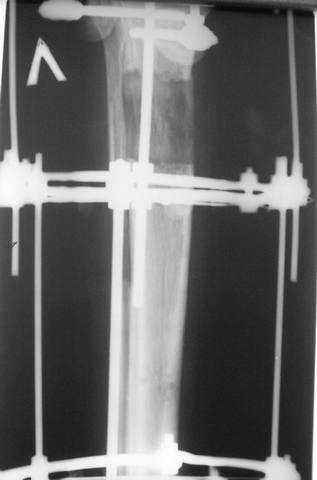

3,4 - через 4 недели наложен спице-стержневой аппарат, произведена остеотомия большеберцовой кости в верхней трети, раны зажили, проводилась дистракция в аппарате.

5. Ну и чтобы не быть голословным. Молодой человек подорвался на фугасе (Чечня, 2005 год). Свежие рентгенограммы:

Соответственно ожоги и дефект мягких тканей, переломы костей стопы и пр. Наложили аппарат

Илизарова (как придется), хирургически обработали и героически заживляли мягкие ткани с многочисленными кожными пластиками. В итоге через полгода я принял его вот таким: